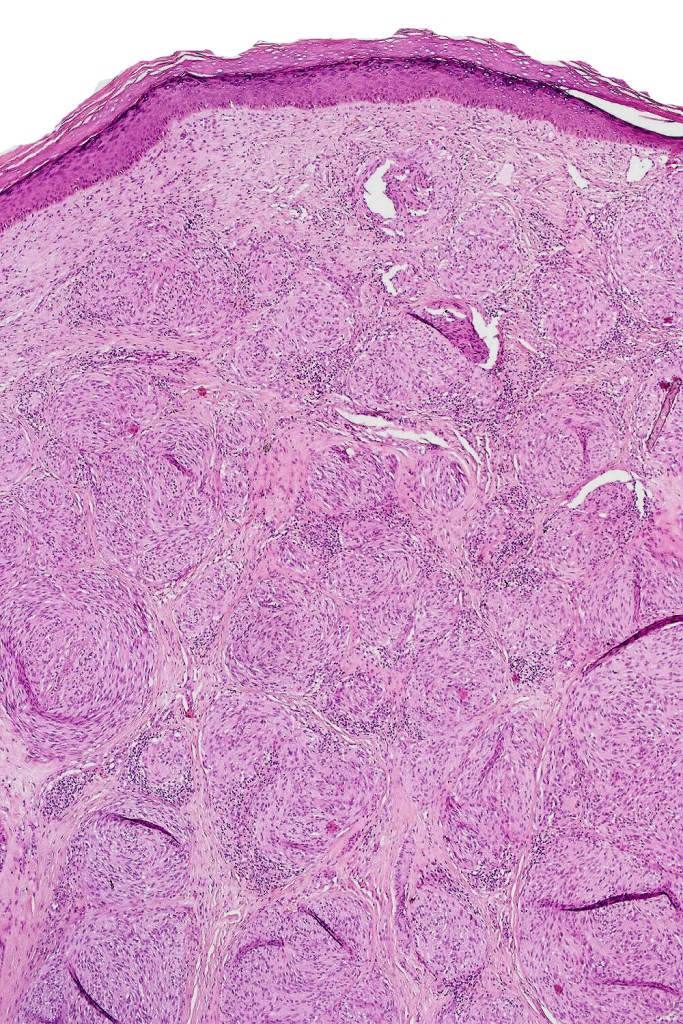

•Sharply circumscribed (begins and ends with a nest), symmetrical dome-shaped lesion. Symmetry is both horizontal and vertical (see image below)

•Wedge-shaped with the base uppermost or sometimes plaque-shaped silhouette

•Matures with depth-often best recognized at scanning/low power magnification & readily confirmed with S100 or MART1

•Hyperkeratosis & acanthosis, sometimes very marked

•Superficial vascular ectasia very frequently present

•Junctional nests often vertically orientated, dyscohesive with a surrounding retraction artifact